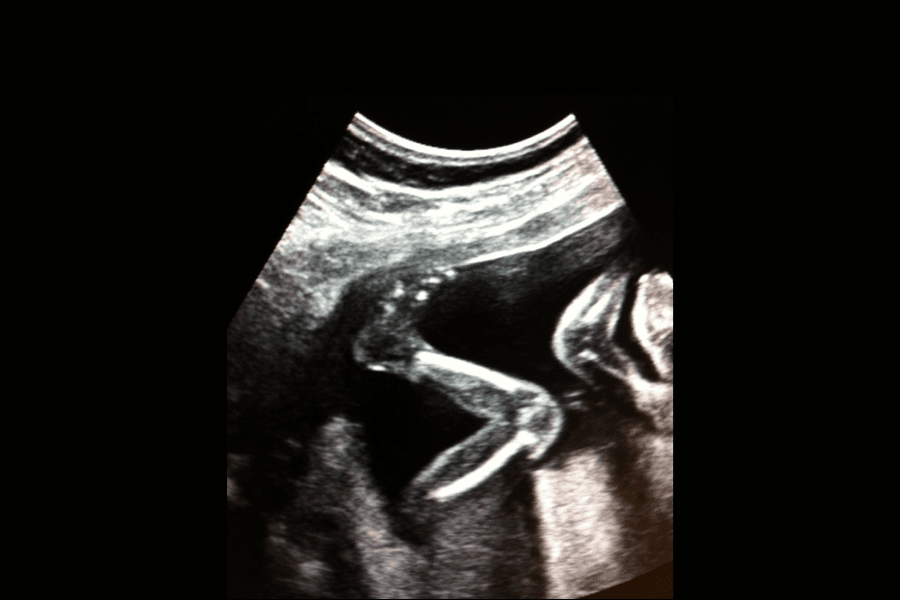

To, jak dziecko porusza się w łonie mamy, jest kwestią bardzo indywidualną. Zarówno intensywność, jak i częstotliwość ruchów jest inna w przypadku każdego malucha. Większość ruchów jest na tyle słaba, iż trudno je poczuć. Dziecko potrafi co prawda kopnąć, ale to za pomocą owych mniejszych ruchów ćwiczy masę innych umiejętności: oddychanie, połykanie, chwytanie, ssanie. Kopniaki to nie wszystko!

To, jak przyszła mama odczuwa aktywność swojego potomka, zależy od wielu czynników: osobowości malucha, wielkości macicy, pozycji, jaką dziecko w niej przyjęło oraz położenia łożyska.

Mniej indywidualną kwestią jest natomiast to, kiedy powinno się poczuć ruchy dziecka. Większość kobiet po raz pierwszy doświadcza tego magicznego momentu koło 20 tygodnia ciąży. Jeśli łożysko położone jest przy przedniej ścianie macicy, możesz doznać tego nieco później. Nie będzie to jednak mieć wpływu na intensywność odczucia.

Od tego momentu powinnaś czuć ruchy dziecka coraz częściej, aż zaczniesz odczuwać je codziennie – następuje to zazwyczaj koło 25 tygodnia ciąży. Stan ten powinien utrzymać się do rozwiązania. Zaczniesz orientować się, kiedy Twoje dziecko śpi, a kiedy jest aktywne. Zazwyczaj maluszki dokazują, gdy mama udaje się na spoczynek. W ciągu dnia, gdy zaprzątają Cię różne sprawy, możesz odnieść wrażenie, iż dzieciątko się nie rusza. Zmieni się to jednak, gdy sama zwolnisz tempo i odpoczniesz chwilę.